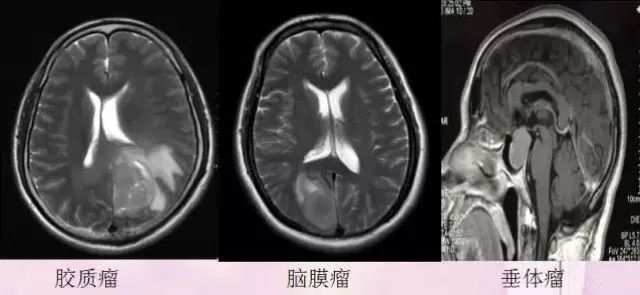

8、比较常见的颅内肿瘤

脑梗塞、脑肿瘤、炎症、变性病、先天畸形、外伤等中枢神经系统病变,是最早应用于MRI检查的系统,目前积累了丰富的经验,对病变的定位、定性诊断较为准确、及时,可发现早期病变。